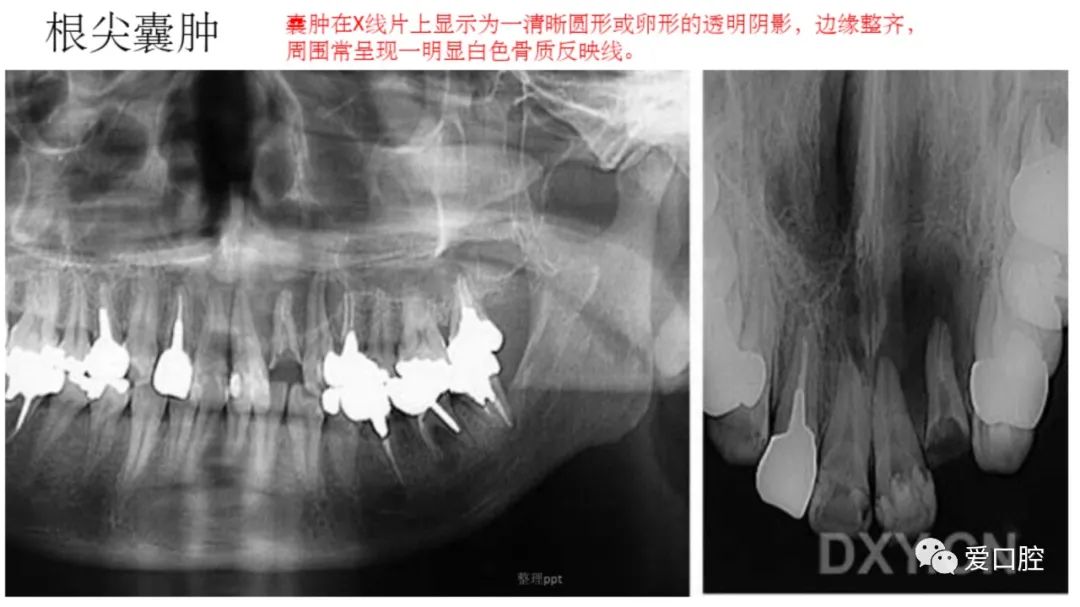

口腔小技巧 | 口腔科常见的病例影像!